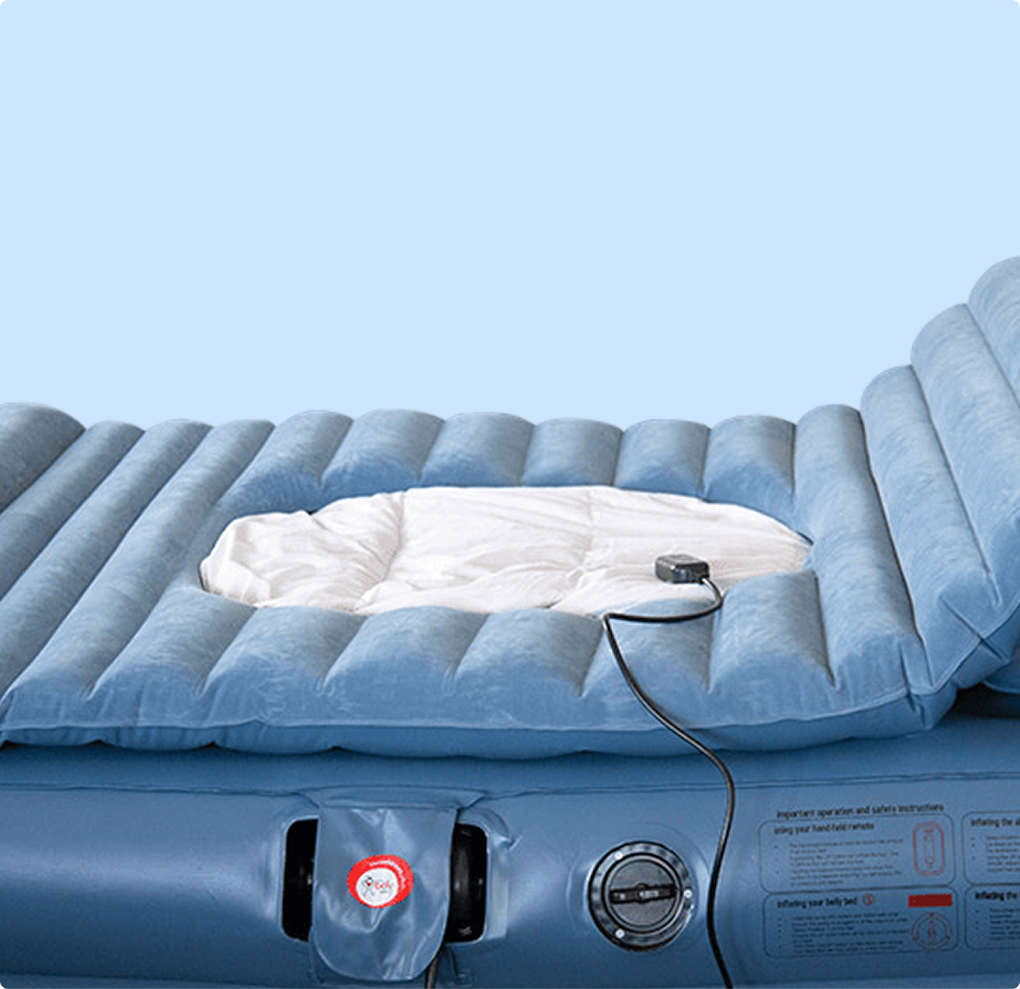

Advancing world-first breakthroughs, faster

World first breakthroughs aren't designed to sit on the lab bench forever. They need to be in the hands of doctors and patients - saving lives and transforming outcomes. We help you get there.

Medical innovations are not one-size-fits-all, so why should your clinical trials be? At Mobius, our team uses their deep expertise to develop a clinical trial strategy tailored for you.